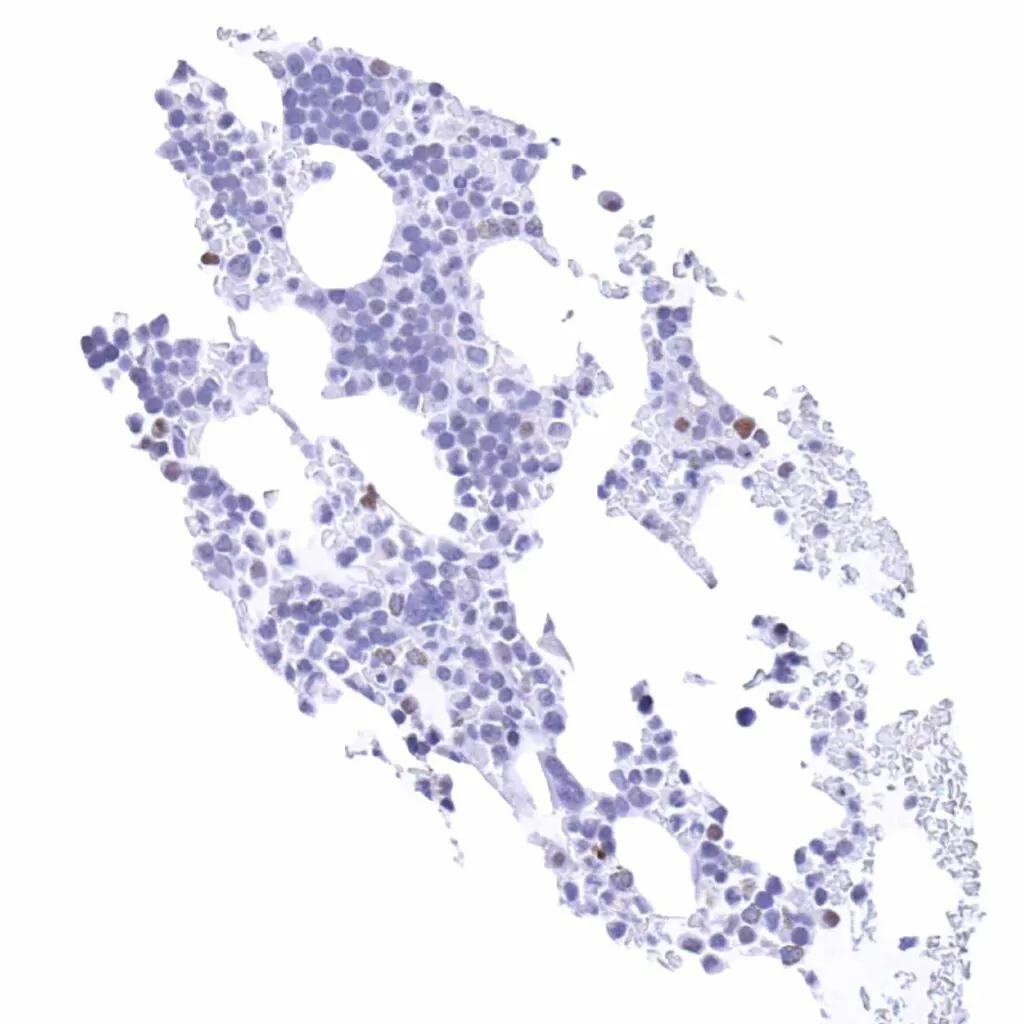

Lymph node – Weak Cyclin E1 staining of only a small fraction of cells